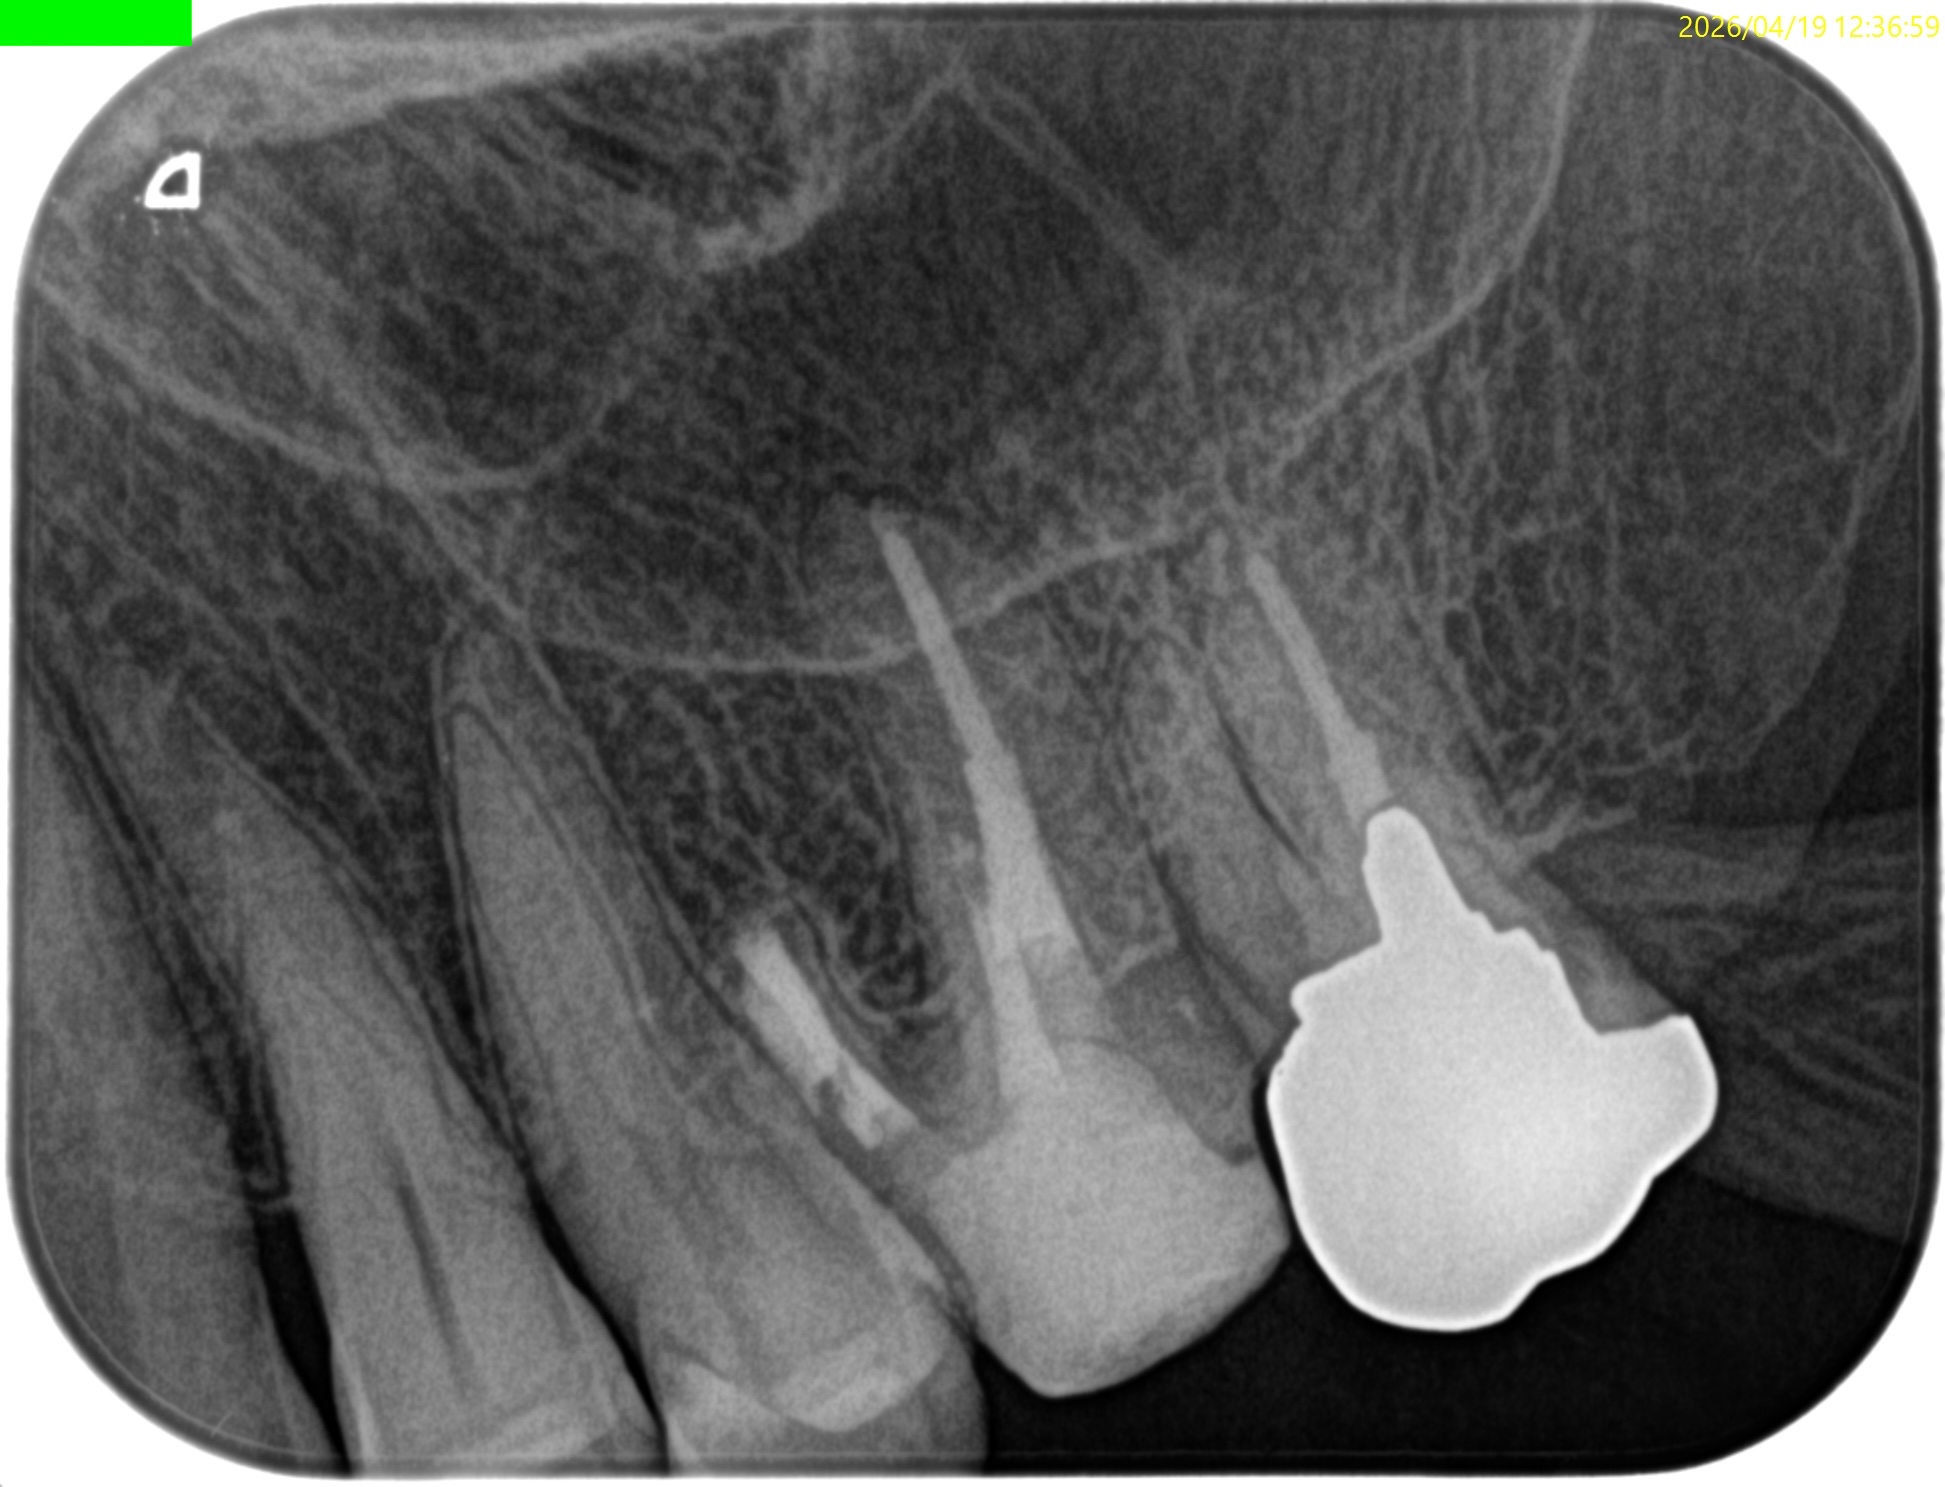

#14 Post-op 2yr recall(2026.4.19)

初診時と比較した。

歯槽骨の欠損は完治した。

術前の臨床症状も消失した。